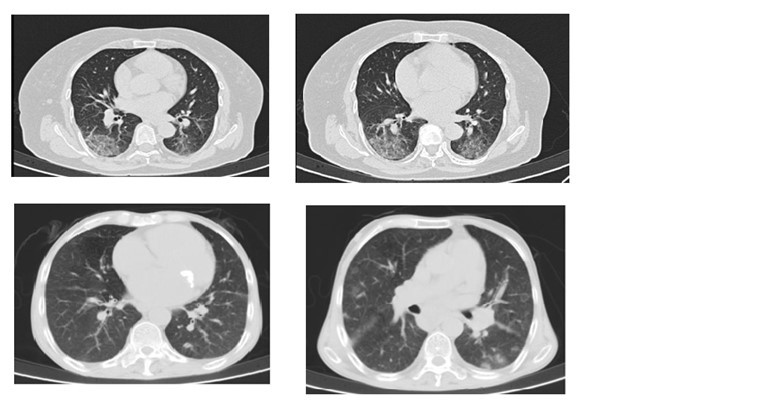

COVID commonly involves bilateral multifocal areas of the lungs. Single lobe involvement was also observed in a small number of patients. The right lower lobe, being a short and thick anatomic structure, can easily be invaded by the virus. Sub-pleural distribution of the disease is commonly seen because of possible location of target cells in the lower airway. Lesions around the bronchovascular pathways can be explained by the spread of infection along the intralobular interstitial tissues. Inflammation starts by early invasion of cortical pulmonary airways and alveolar epithelium, and gradual extension towards the central area.

Typical findings:

- Ground-glass opacities with multifocal and peripheral or basal distributions

- Crazy paving

- Spider web

- Consolidation

- Reversed halo

The most common CT findings in COVID-19 are ground glass opacities and consolidation noticed in 95% and 72% of the patients respectively. Ground glass opacities have been considered to be the result of serous inflammatory exudative reaction from lung alveoli. Copious amounts of such inflammatory exudation ultimately forms consolidation. Studies have reported prominent bilateral consolidation on CT scans in ICU patients. Ground-glass opacities and little areas of consolidations are seen in patients with mild symptoms of the infection not mounting to the admission.

Clinical implications of these findings are that manifestation of the disease in early stage are ground-glass opacities and as the severity progresses consolidation becomes eminent in wider areas. In other words, such changes are predictive of rising possibilities of critical complications like acute respiratory distress syndrome or acute lung injury.

In a retrospective study, authors found patients with initial negative RT-PCR having mostly ground glass opacities and small areas of consolidation as compared to patients with positive initial RT-PCR results. Patients with mild lung injury as suggested by smaller consolidation areas on CT scan are having higher chances of getting negative initial RT-PCR result.